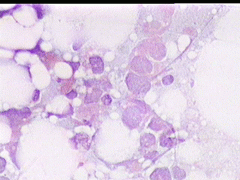

Aσθενής T.E., ετών 47, προσέρχεται το 1998 για α΄φορά στο ιατρείο μας, επειδή κάτι ψηλαφά στον μαστό.

Κατά την κλινικο - υπερηχογραφική διερεύνηση μεταξύ κάτω έξω και κάτω έσω 4μοριου στον δεξιό μαστό. σχετικώς κινητό οζίδιο διαμέτρου 13 χιλ

Yπερηχογραφικώς καλοήθης εικόνα, όπως σε ιναδένωμα

Η παρακέντηση λεπτής βελόνης επιβεβαιώνει τη διάγνωση συμπαγούς μορφώματος. Το ελάχιστο υλικό επιστρώνεται σε αντικειμενοφόρο πλάκα, στεγνώνει στον αέρα με και βάφεται κατά Papanicolaou.

Δείγμα μικροσκοπικών εικόνων: